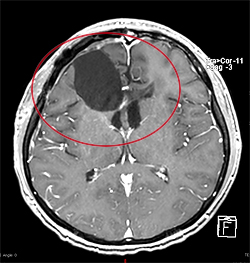

悪性腫瘍の手術前

手術後

放射線・化学療法後